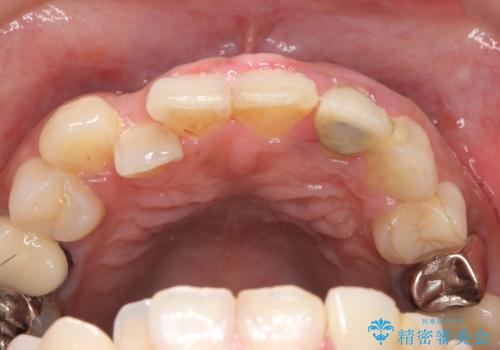

左上2番目の歯は歯根が破折してため抜歯し、左上123のブリッジによる欠損補綴を行いました。

左上4、5番目の歯は根尖病変を認めたため再根管治療を行い、オールセラミッククラウンによる補綴を行いました。

なお左上4に関しては縁下歯質を改善するため、歯冠挺出を行っております。